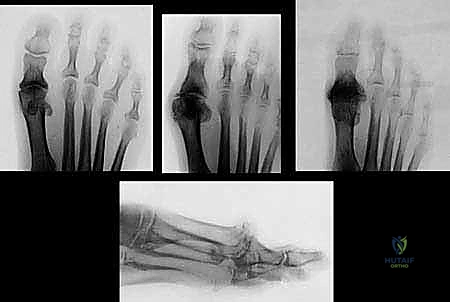

| المرحلة (Grade) | الأعراض السريرية | التغيرات الإشعاعية (أشعة X) | نطاق الحركة (Dorsiflexion) |

|---|---|---|---|

| المرحلة 0 | ألم خفيف عرضي، لا يوجد ألم أثناء المشي العادي. | طبيعية أو تغيرات طفيفة جداً. | طبيعي أو مقيد بشكل بسيط (40-60 درجة). |

| المرحلة 1 | ألم متقطع، خاصة عند أقصى درجات الانثناء. | نتوء عظمي ظهري صغير، الحيز المفصلي سليم. | تقييد بسيط (30-40 درجة). |

| المرحلة 2 | ألم معتدل إلى شديد، تيبس ملحوظ، ألم قبل الوصول لأقصى انثناء. | نتوء عظمي واضح، تضيق في الحيز المفصلي الظهري. | تقييد ملحوظ (10-30 درجة). |

| المرحلة 3 | ألم شديد ومستمر حتى في أوقات الراحة، صعوبة بالغة في المشي. | تضيق شديد في الحيز المفصلي بالكامل، نتوءات عظمية كبيرة، تكيسات تحت الغضروف. | تقييد شديد (أقل من 10 درجات). |

| المرحلة 4 | نفس أعراض المرحلة 3، مع ألم دائم حتى عند تحريك المفصل سلبياً (بواسطة الطبيب). | تدمير كامل للمفصل، اختفاء الحيز المفصلي تماماً. | تيبس شبه كامل. |

- التصوير الإشعاعي (X-rays):

وهو الأداة الذهبية لتشخيص تيبس إبهام القدم. تُظهر الأشعة السينية بوضوح: - تضيق المسافة بين العظام (دليل على تآكل الغضروف).

- وجود النتوءات العظمية (Bone Spurs).

- أي تكيسات عظمية أو تشوهات في شكل المفصل.